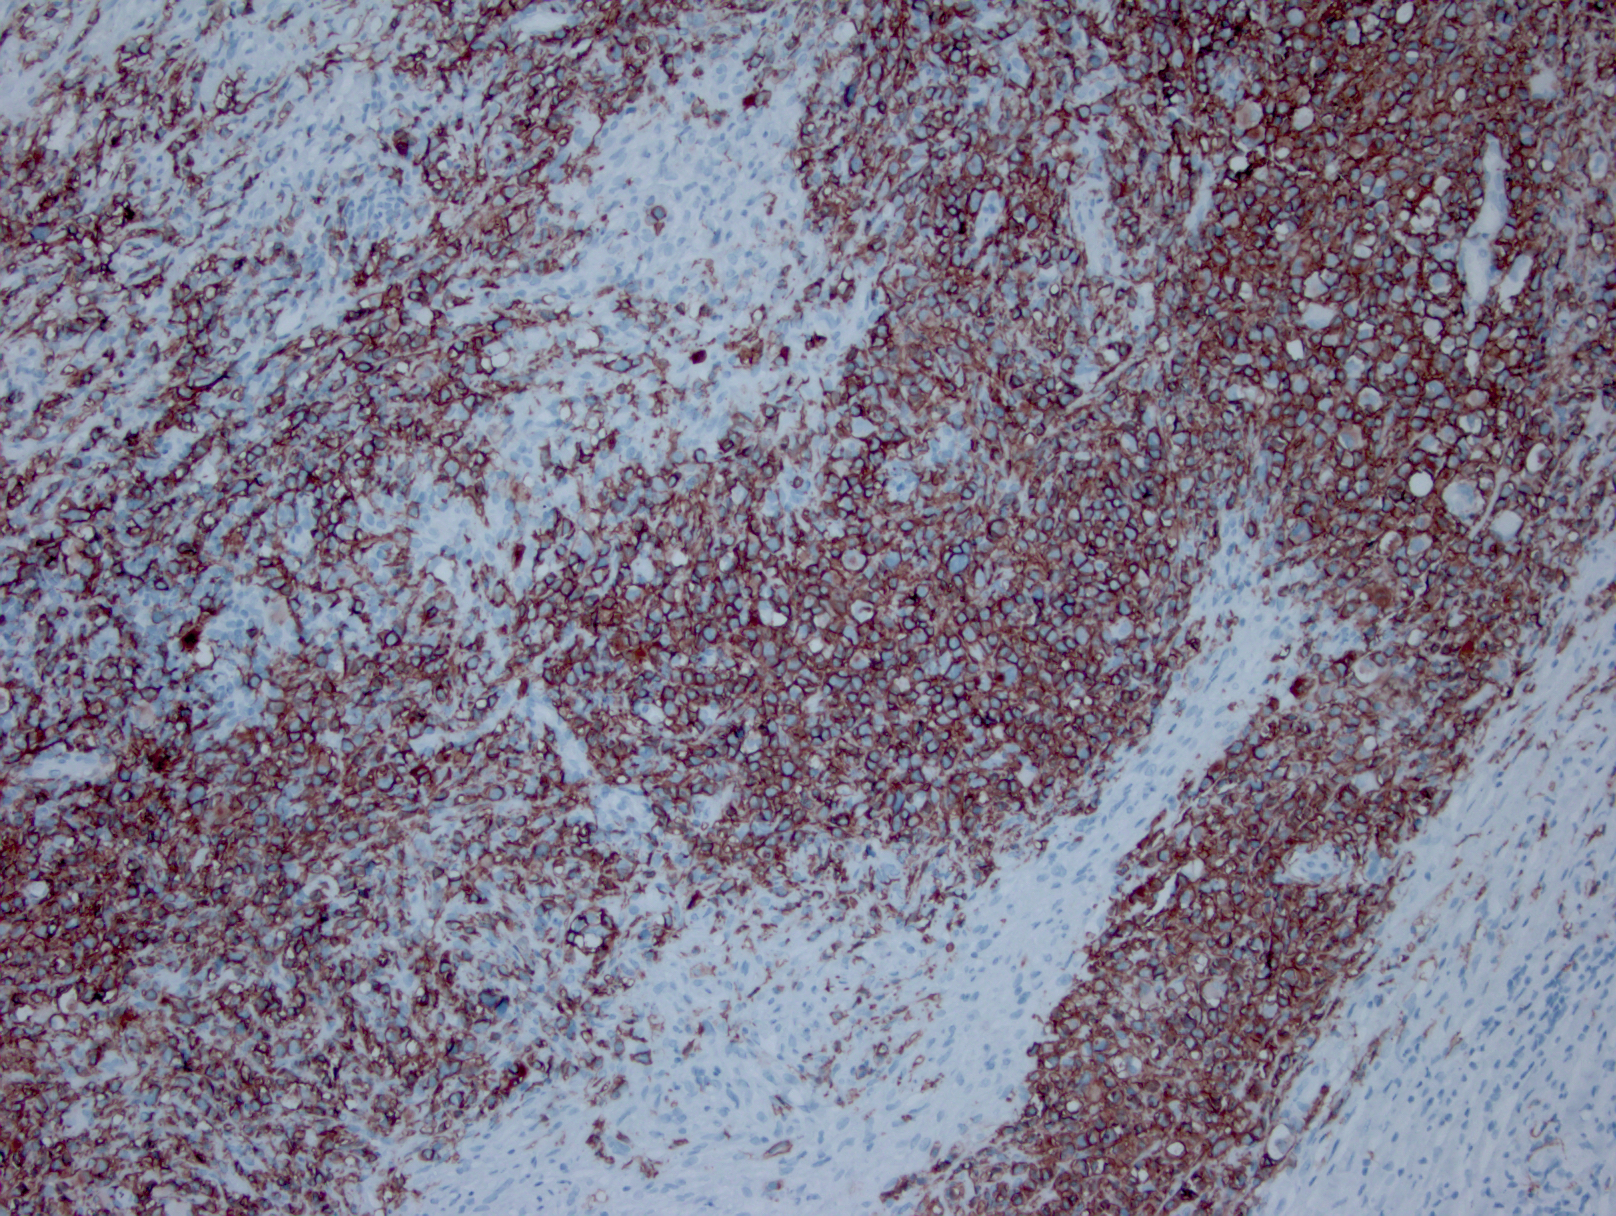

免疫表型:肿瘤细胞表达“混合”抗原,符合弥漫大 B 细胞淋巴瘤和经典霍奇金淋巴瘤的双重特征。CD45+,CD30+,多数 CD15 阳性,CD20 和 CD79a 通常阳性,PAX5. Oct2. 和 BOB1 一般也阳性。Bcl-6+/-, CD10-。 EBER 一般阴性(但也有极少阳性病例报道)。

免疫组织化学染色:

肿瘤细胞表达“混合”抗原,符合弥漫大 B 细胞淋巴瘤和经典霍奇金病的双重特征。CD45+,CD30+,多数 CD15 阳性,CD20 和 CD79a 通常阳性,PAX5. Oct2. 和 BOB1 一般也阳性。Bcl-6+/-,CD10-。EBER 一般阴性。